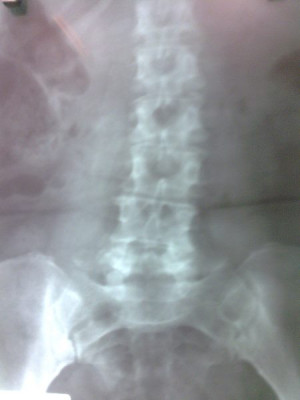

Radiografías con enfoque en fisiatría

Envíado por Dr. Hernán Darío Sánchez Ramos